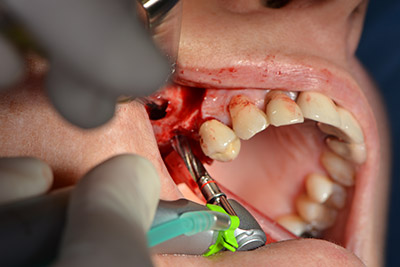

Le vie indicate di seguito sono realizzate con una perforazione a velocità ridotta, pari a 300 rpm. In questa fase Implantmed dimostra la sua grande affidabilità. È possibile predefinire il protocollo chirurgico: per selezionare le varie posizioni, basta premere la lettera “P” con il controllo a pedale (da fig. 10 a 11).

Il passaggio successivo consiste nel posizionamento dell'impianto, che nel nostro studio prevede una potenza pari a 32 Ncm (fig. 12).